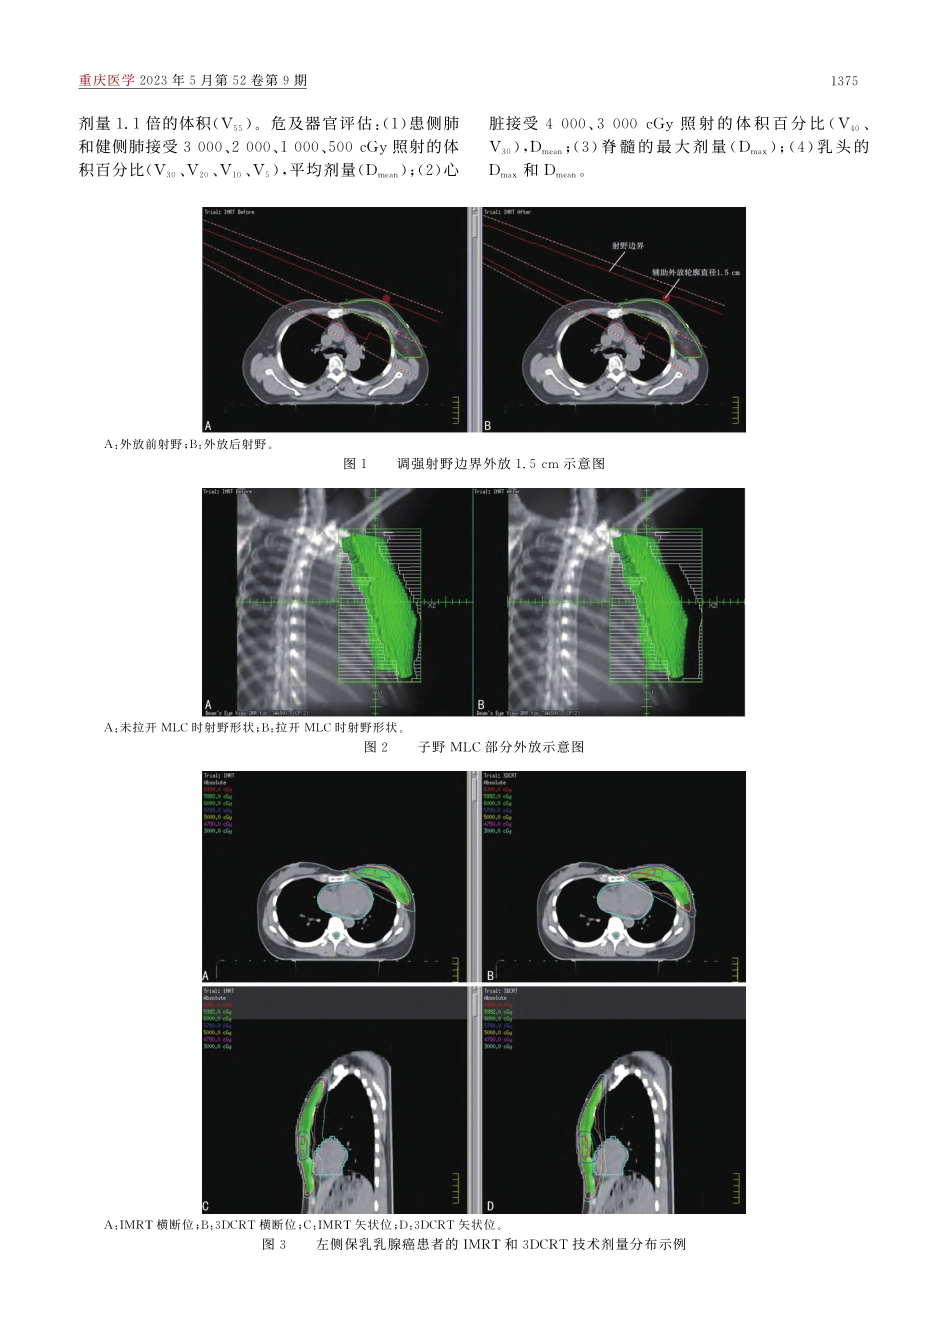

论著·临床研究doi:10.3969/j.issn.1671-8348.2023.09.019网络首发https://kns.cnki.net/kcms/detail/50.1097.r.20230328.1115.012.html(2023-03-28)乳腺癌保乳术后IMRT和3DCRT的剂量学比较*董晓庆,胡杰,林清△(同济大学附属第十人民医院放射治疗科,上海200072)[摘要]目的比较调强放疗(IMRT)技术和三维适形放疗(3DCRT)技术在乳腺癌保乳术后放疗的剂量学差异。方法选取2017年8月至2019年9月在该院行保乳术后放疗的乳腺癌患者80例,同一影像分别设计IMRT和3DCRT计划,对比评估靶区均匀性指数(HI)、适形度指数(CI)、2%、98%靶区体积所受照剂量(D2、D98),以及患侧肺、健侧肺、心脏、脊髓和乳头的剂量。结果与3DCRT技术相比,IMRT技术下全乳腺计划靶区(PTV)、瘤床加量计划靶区(PTVb)的HI降低,CI升高,PTV抠除PTVb区域(PTV-PTVb)的D2、PTV-PTVb中接近处方剂量1.1倍的体积(V55)降低[V55:145.10(100.84,227.25)cm3vs.247.84(183.35,353.12)cm3],差异均有统计学意义(P<0.05)。与3DCRT技术相比,IMRT技术下患侧肺3000、2000cGy照射的体积百分比(V30、V20)和平均剂量(Dmean)降低,心脏4000cGy照射的体积百分比(V40)、V30和Dmean降低,乳头的最大剂量(Dmax)、Dmean降低,脊髓的Dmax升高,差异均有统计学意义(P<0.05)。结论与3DCRT技术相比,IMRT技术在乳腺癌保乳术后放疗中更能提高靶区均匀性和适形度,降低靶区高剂量区体积,更好地保护危及器官。[关键词]乳腺癌;调强放射治疗;三维适形放射治疗;剂量学;危及器官[中图法分类号]R737.9[文献标识码]A[文章编号]1671-8348(2023)09-1373-06DosimetriccomparisonbetweenIMRTand3DCRTafterbreast-conservingsurgeryforbreastcancer*DONGXiaoqing,HUJie,LINQing△(DepartmentofRadiothera...